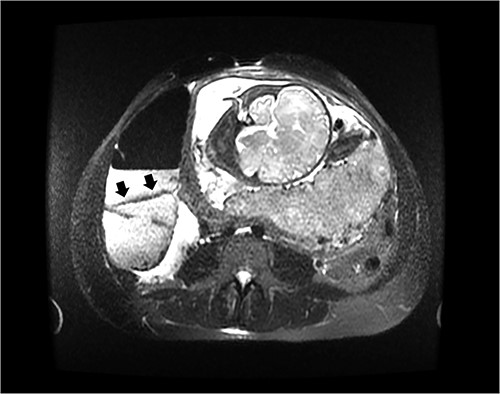

On hospital day 2, the patient became obstipated, and her abdominal exam had notable distension with persistent right upper quadrant tenderness. An abdominal magnetic resonance imaging (MRI) was performed revealing dilated small intestine with air-fluid levels and an inverted-appearing, prominent cecum (Figs. 1 and 2). The patient was diagnosed with an acute abdomen from probable cecal volvulus versus appendicitis and was urgently taken to the operating room for cesarean section (c-section) to facilitate abdominal exploration. After delivery of the child, a cecal bascule was found, with a severely distended cecum (Fig. 3). Because the cecum and ascending colon were deserosalized, a right hemicolectomy with primary ileocolic anastomosis was performed. The patient had return of bowel function on post operative day 5 and was discharged home on day 7.

Axial image of an abdominal MRI on a 36-week pregnant patient with a dilated cecum anteriorly displaced to the ascending colon. Arrows mark the point of inflection.